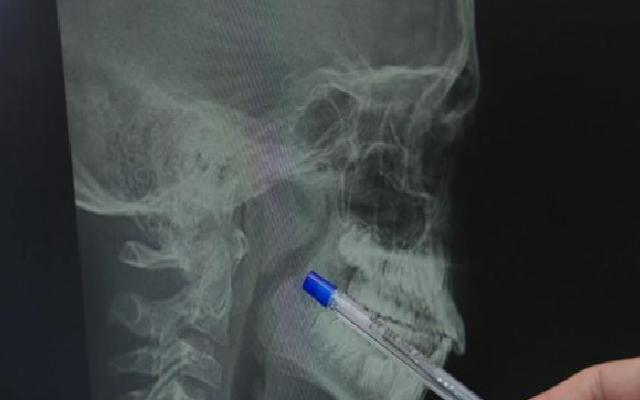

Çocuklarda bademcik ve geniz eti büyümesinin, solunum yollarını ciddi şekilde tıkadığı durumlarda, özellikle uyku apnesi veya nefes durması gibi yaşamı tehdit eden sorunlar ortaya çıkabilir. Bu durumda, cerrahi müdahale kaçınılmaz hale gelir. Ancak, her durumda bademcik alınması gerekmeyebilir.

Ameliyat teknikleri konusunda uzmanlar, geniz eti operasyonlarının klasik yöntemler veya modern teknolojilerle yapılan buharlaştırma teknikleri kullanılarak gerçekleştirilebildiğine işaret ediyor. Bademcik ameliyatlarında ise, sıcak ve soğuk yöntemler tercih ediliyor. Soğuk yöntem, ameliyat sonrası yaşanan ağrı ve iyileşme sürecini daha konforlu hale getiriyor.